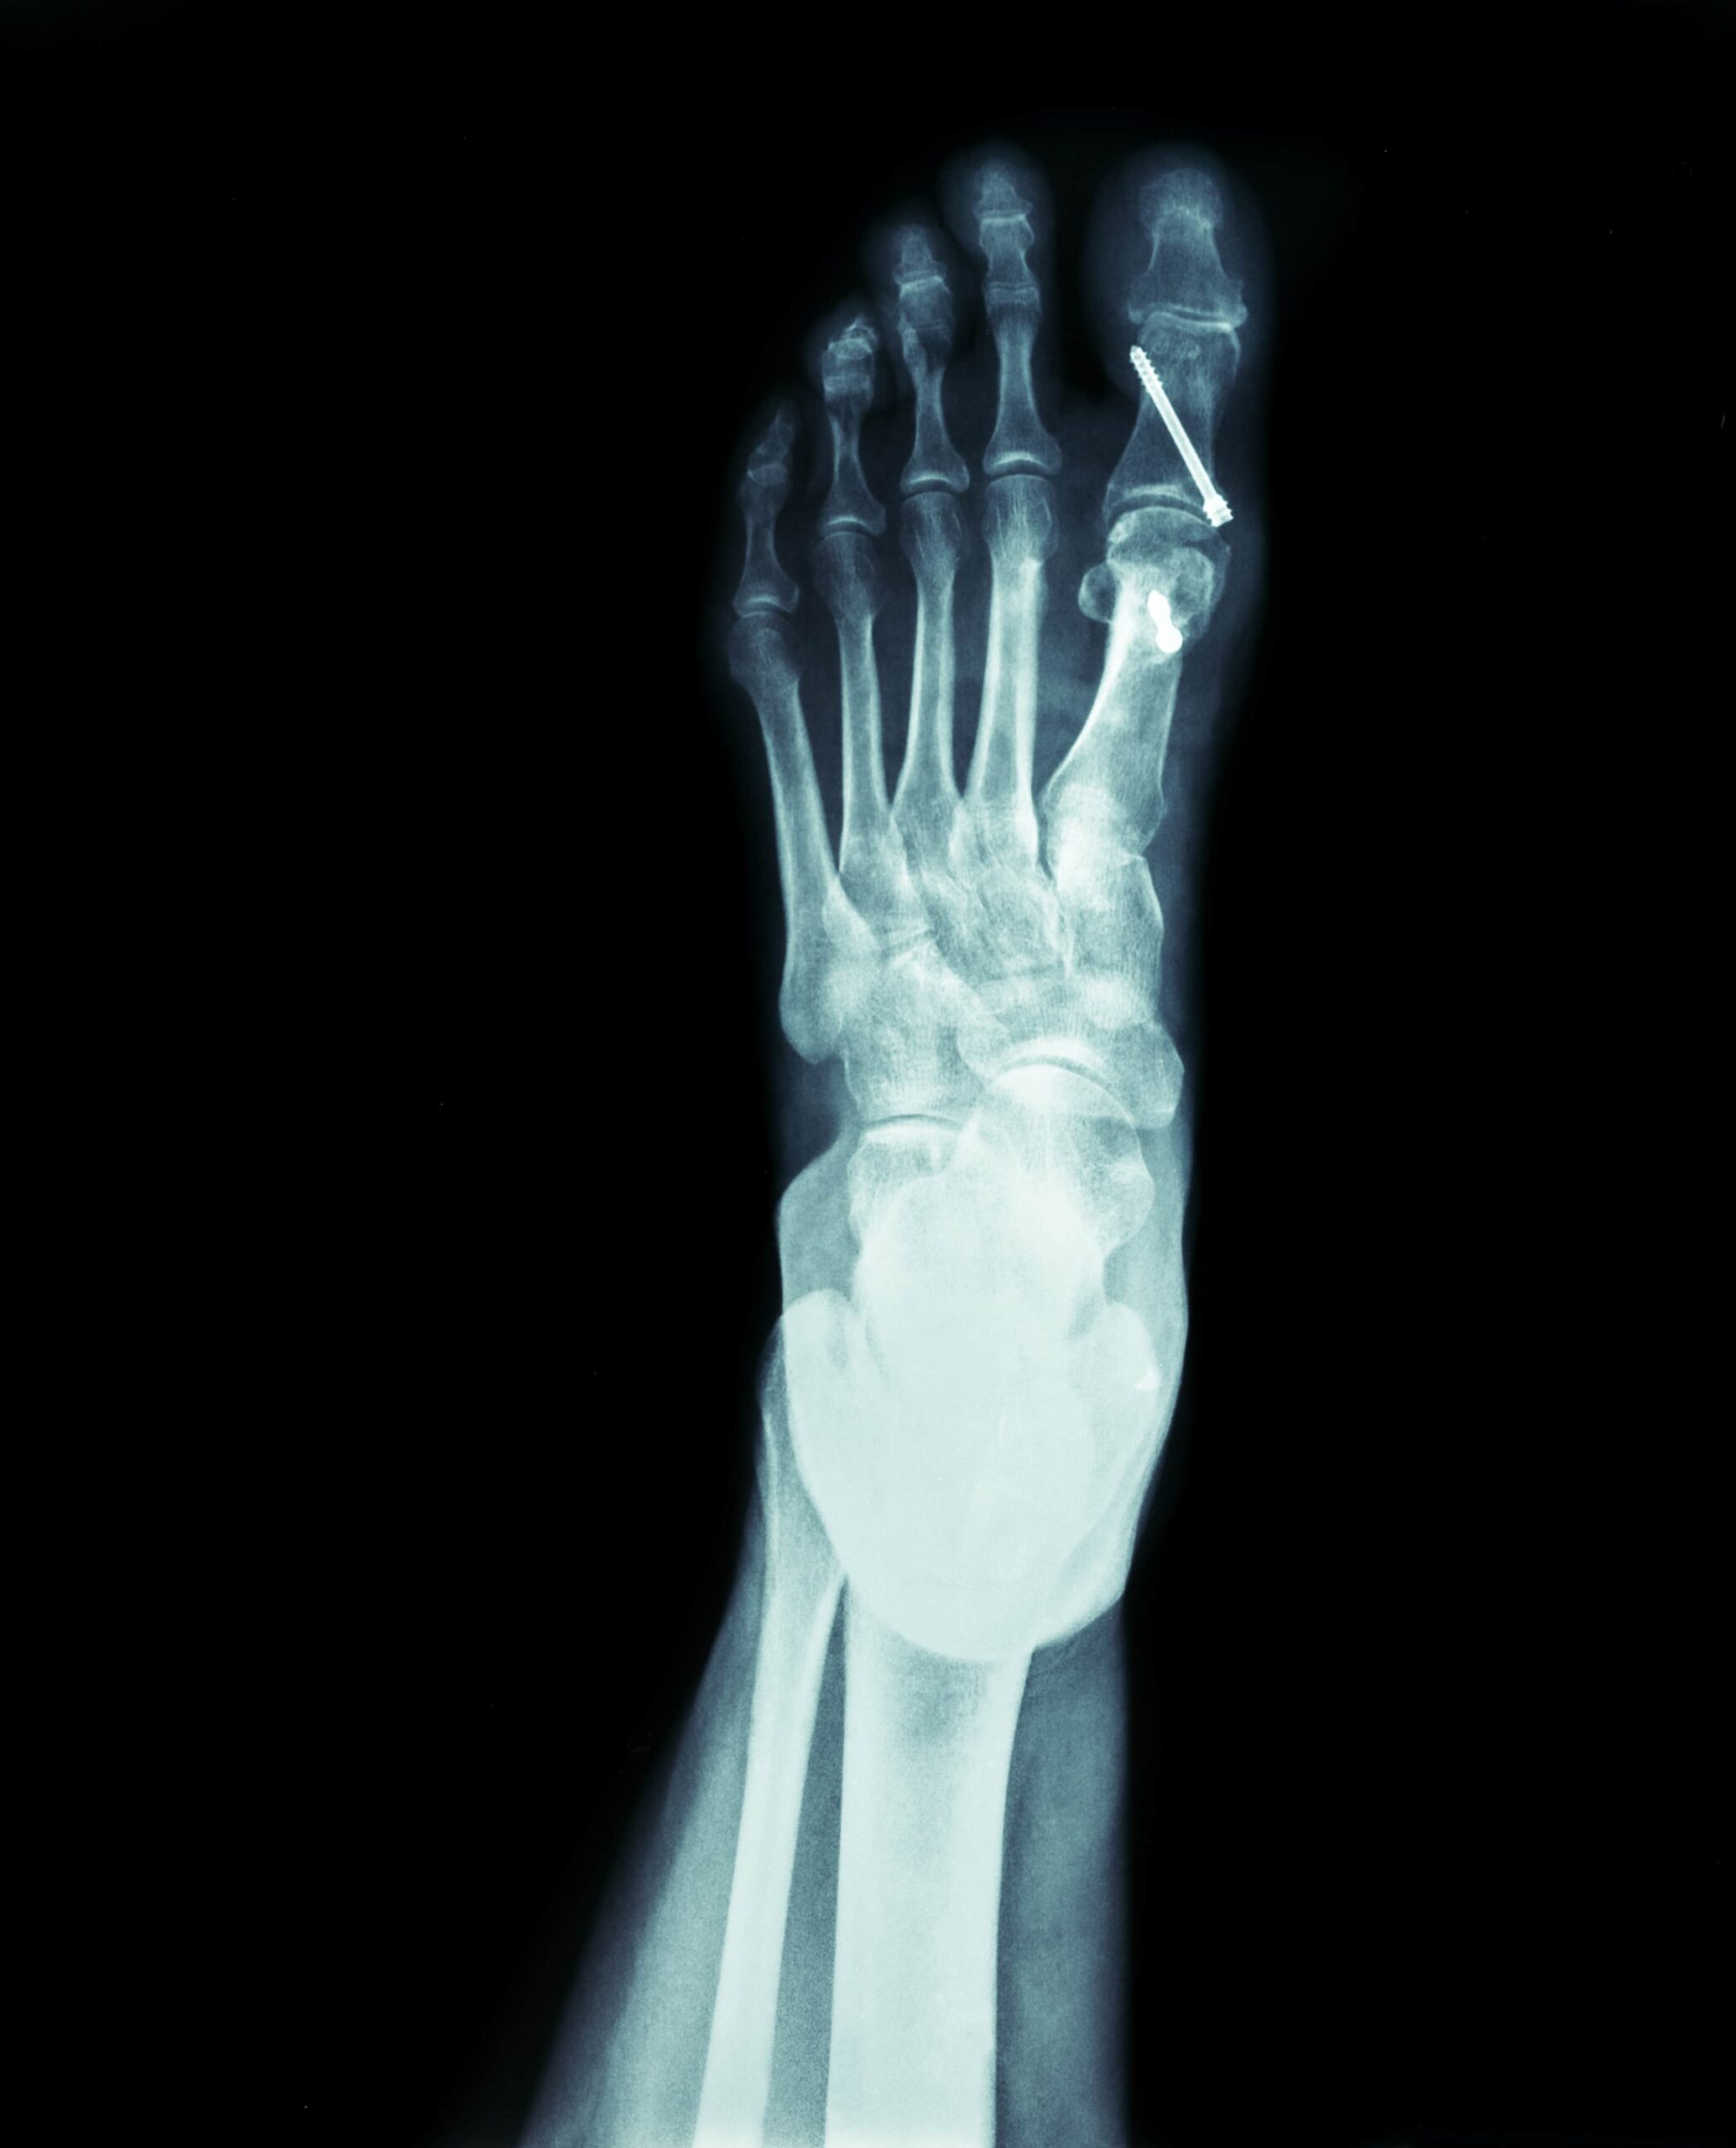

- Foot and Ankle Osteotomy:

- Corrects deformities like bunions, flat feet, or clubfoot.

Procedure Overview

- Preoperative Evaluation:

- X-rays, CT scans, or MRIs are used to assess the deformity.

- Surgical Steps:

- Under anesthesia, the surgeon makes an incision at the affected area.

- The bone is cut and repositioned using metal plates, screws, or rods for stabilization.